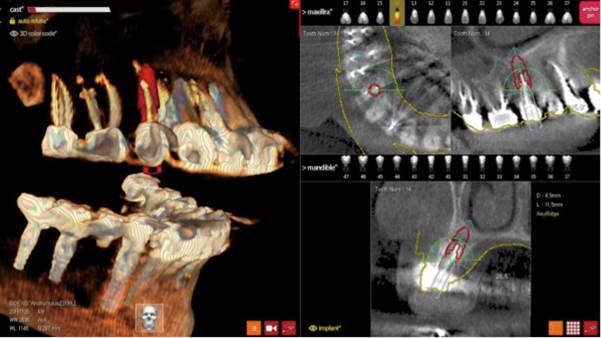

Clinical case: Digital Data Save concept in upper jaw premolar area

- Courtesy of Dr. Lysov Alexander Dmitrievich & Dr. Sofronov Matvey Vitalievich, Russia -

Keywords

AnyRidge, R2GATE, R2GATE guide, ISQ value, initial stability, immediate loading, KnifeThread, maxillary posterior, #14, Digital, Dr. Lysov Alexander Dmitrievich, Dr. Sofronov Matvey Vitalievich, zirconia abutment, CAD/CAM crown

Products used

AnyRidge implant system, R2GATE, Digital prosthesis

“AnyRidge & R2GATE show stable results

after immediate extraction, immediate implant placement, & immediate loading,

even with low bone density.”